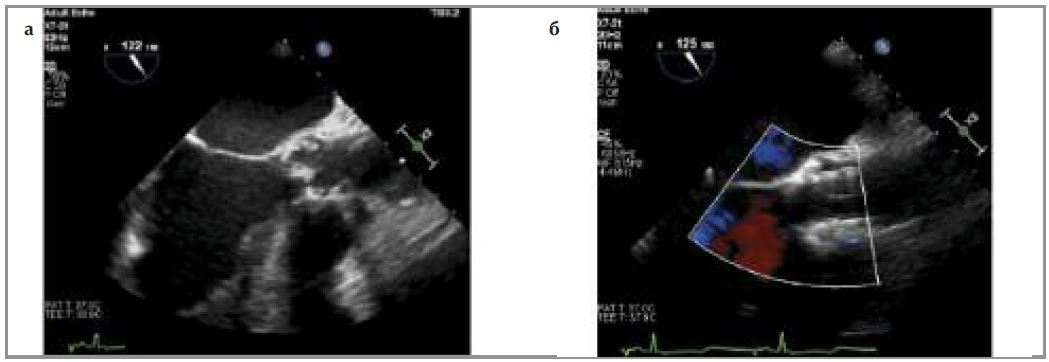

В условиях общей анестезии выполнен доступ к бедренной артерии, через установленный интродьюсер в аортальную позицию заведен баллонный катетер, выполнена предилатация, после которой по данным чреспищеводной ЭхоКГ (ЧпЭхоКГ) в области левого коронарного синуса визуализировано флотирующее образование – фрагмент створки АК (рис. 5, а).

Рис. 5. Интраоперационная ЧпЭхоКГ: а - стрелкой отмечен флотирующий фрагмент левой коронарной створки АК непосредственно после балонной вальвулотомии АК; б - функционирующий биопротез АК; дополнительные образования в проекции коронарного синуса не визуализируются.

На системе доставки имплантирован биопротез CoreValve Evolut R 29 мм, последовательно выполнена постдилатация баллонами 20 и 23 мм. При контрольной ЧпЭхоКГ флотирующий элемент не визуализируется (рис. 5, б). При финальной КАГ коронарные артерии проходимы, запирательная функция протеза АК осуществляется в полном объеме (рис. 6).